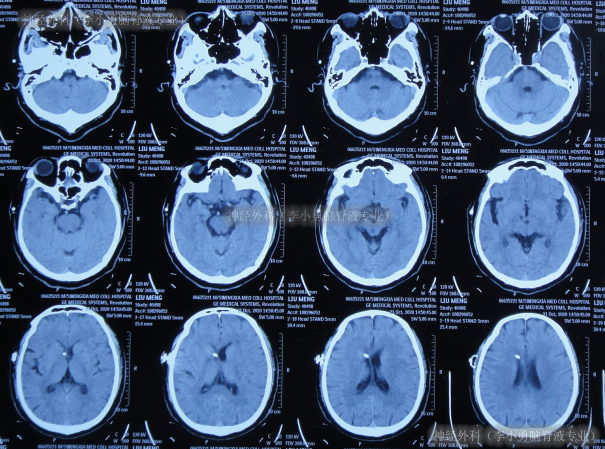

但出院后1个月即2020年12月6日(脑室腹腔分流术后3年零2月),再次出现嗜睡,第3次就诊该院,查头颅CT(片子丢失)后认为脑室系统与1月前相比并未明显扩张,但第2天即2020年12月7日,出现昏迷,大小便失禁,再查头颅CT(图-3)后认为脑室有大。

图-3:2020年12月7日头颅CT